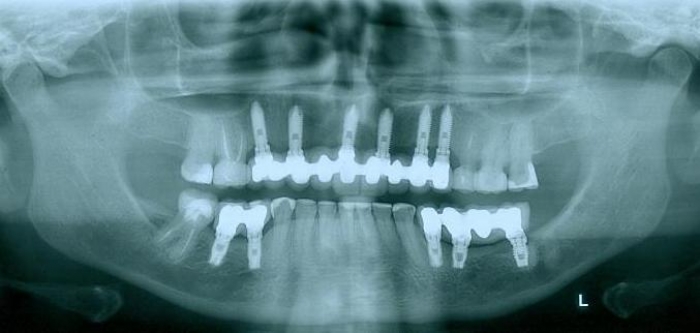

Rx Inicial